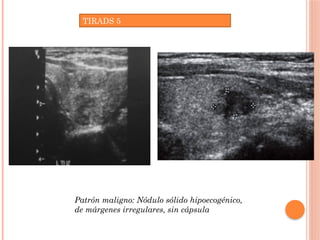

TIRADS 5

Patrón maligno: Nódulo sólido hipoecogénico,

de márgenes irregulares, sin cápsula